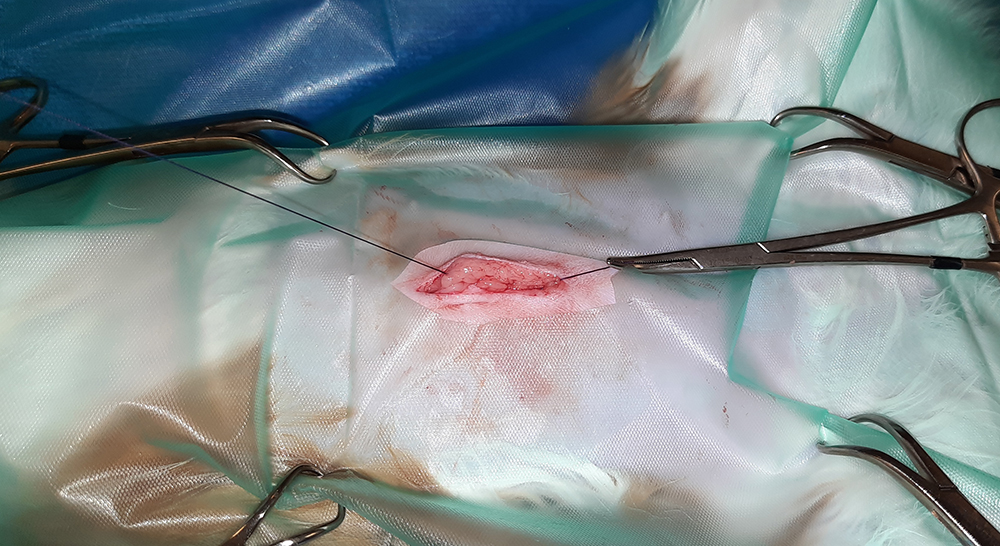

Er wordt een kleine snede gemaakt in de buik, ter hoogte van de navel. Vervolgens worden na elkaar de twee ovaria (=eierstokken) opgezocht, de aanvoerende bloedvaten afgebonden en de eierstokken verwijderd. Hierna wordt de buik in 3 lagen gesloten; de spierlaag, de onderhuid en de huid. Deze laatste wordt onderhuids gesloten met soms een enkele uitwendige knoophechting, zodat er zo min mogelijk hechtingen zichtbaar zijn. Er wordt een wondpleister geplaatst, nadat het wondgebied voorzichtig is schoongemaakt.